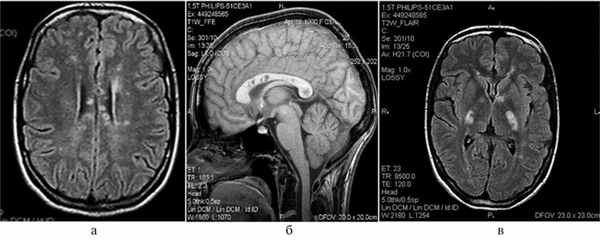

(а) MPT, FLAIR, аксиальный срез: у женщины 27 лет с синдромом Сусака, поступившей в лечебное учреждение с жалобами на головную боль и спутанность сознания, в структуре мозолистого тела определяются множественные гиперинтенсивные очаги. Классическая триада клинических проявлений включает энцефалопатию, двустороннюю тугоухость и окклюзию ветвей артерии сетчатки.

(б) МРТ, постконтрастное изображение в режиме FLAIR, сагиттальный срез: у этой же пациентки определяется классическая локализация поражения - гиперинтенсивные очаги в стволе мозолистого тела. Обратите внимание на контрастирование лептоменингиальнкс, которое может наблюдаться у 50% пациентов. (а) MPT, DWI модульное изображение, аксиальный срез: множественные гиперинтенсивные очаги, многие из которых характеризуются низкими значениями ИКД, что отражает истинное ограничение диффузии в данных участках. Острые очаги повреждения могут имитировать таковые при васкулите.

По данным МРТ головного мозга: многочисленные супра- и инфратенториальные очаги измененного МР-сигнала в центральных отделах мозолистого тела, не накапливающие контрастное вещество (рис. 1). Рис. 1. МРТ головного мозга больной Е. а — на сагиттальном срезе в режиме Т1 во всех отделах мозолистого тела наблюдаются гипоинтенсивные очаги; б — на аксиальном срезе в режиме FLAIR множественные очаги в мозолистом теле с гипоинтенсивным сигналом из центра («кистозная трансформация»); в — на аксиальном срезе выявляются гиперинтенсивные очаги в режиме FLAIR в области внутренней капсулы («жемчужное ожерелье»). При МРТ шейного отдела спинного мозга патологии не выявлено.